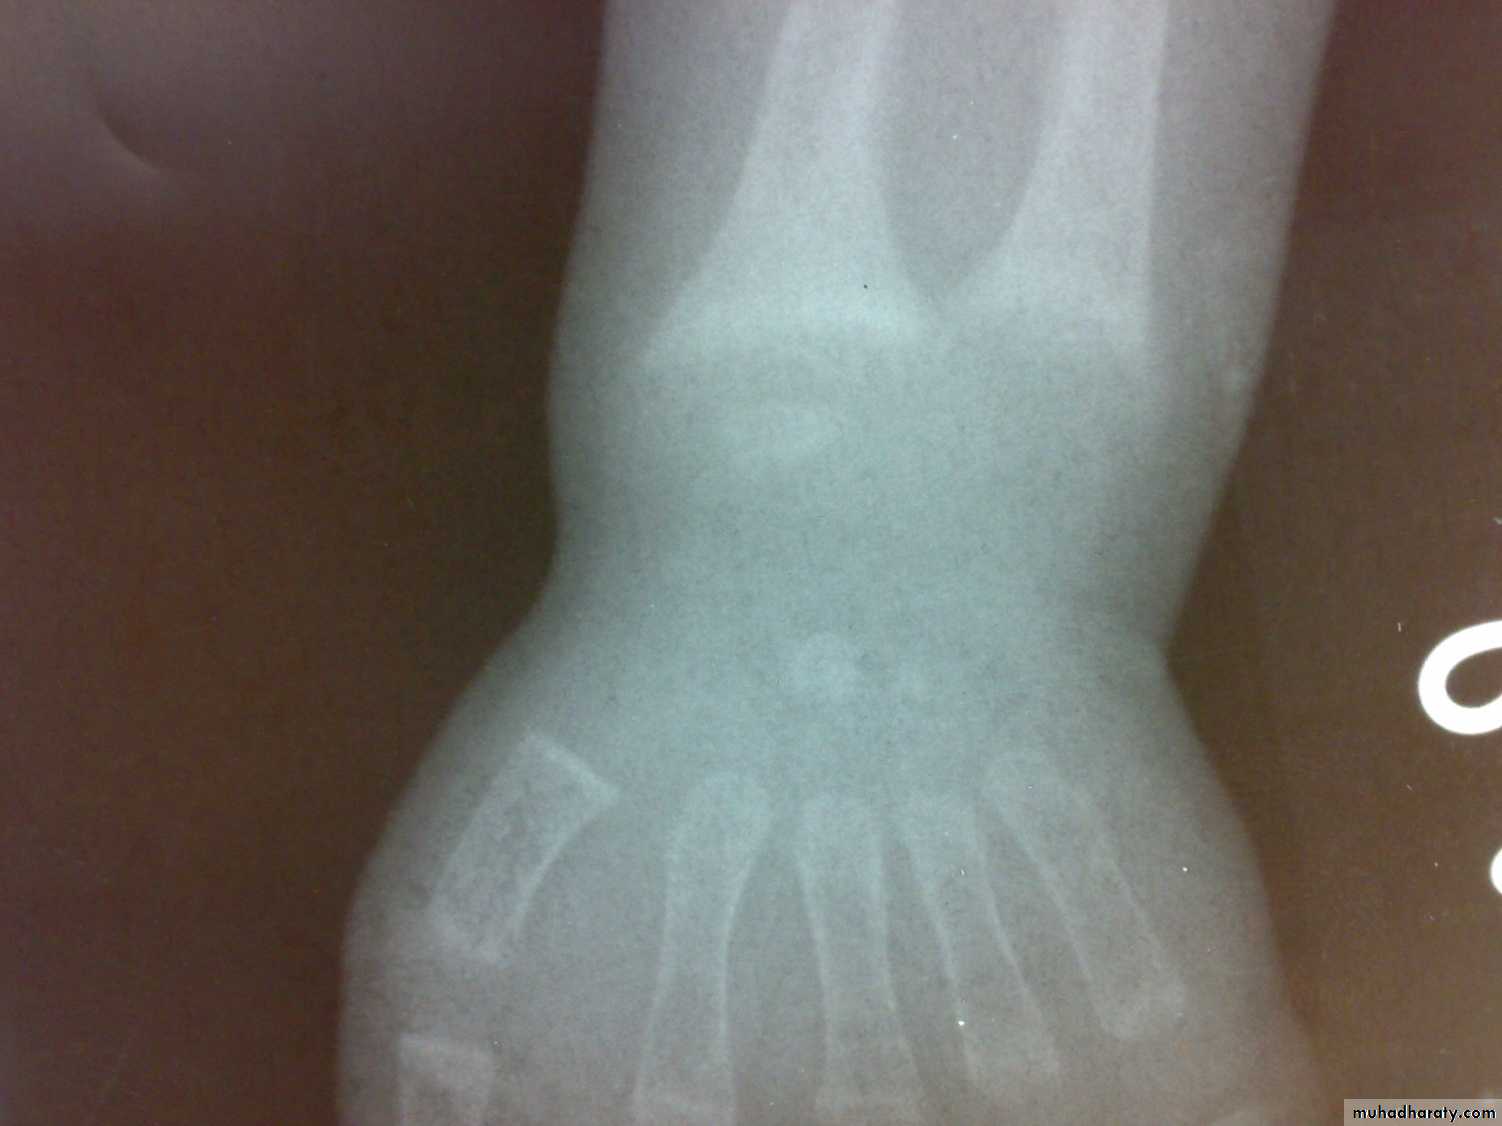

Osteomalacia and ricketsinadequate mineralization of bone

Bone tissue throughout the skeleton is abnormally calcified and therefore soften ( Osteomalacia).

Rickets and Osteomalacia is same disease.

Losser’s zone

decreased serum phosphate

elevated serum alka. Phosphatase.

Ca × p< 2.4 mmol/ L